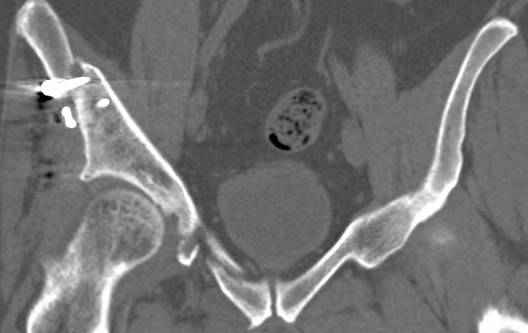

высылаю дополнительно сканы.

итак, второй вариант: высокий двухколонный с вовлечением КПС... Ни одно из основных повреждений не репонировано, кроме задней стенки. Скорее всего попытка реконструкции вертлуги сейчас будет очень травматичной и не очень эфективной, т.е. вероятный риск более значим, чем ожидаемая польза... Лучше подождать, и потом сразу эндопротез